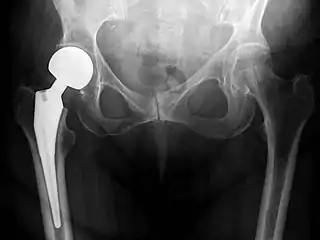

X-ray of the hips, with a right-sided hemiarthroplasty